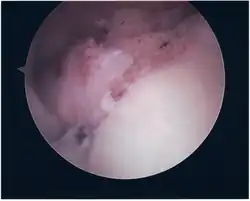

Repair of SLAP Tear

Arthroscopic SLAP Lesion (type 2) repair

Following inspection and determination of the extent of injury, the basic labrum repair is as follows.

• The glenoid and labrum are roughened to increase contact surface area and promote re-growth.

• Locations for the bone anchors are selected based on number and severity of tear. A severe tear involving both SLAP and Bankart lesions may require seven anchors. Simple tears may only require one.

• The glenoid is drilled for the anchor implantation.

• Anchors are inserted in the glenoid.

• The suture component of the implant is tied through the labrum and knotted such that the labrum is in tight contact with the glenoid surface.